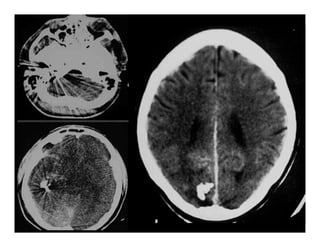

NHỒI MÁU NÃO TỤ MÁU NGOÀI MÀNG CỨNG

Chấn thương sọ não

Đậm độ cao/ Xuất huyết não

Đậm độ thấp/ Phù-dập não